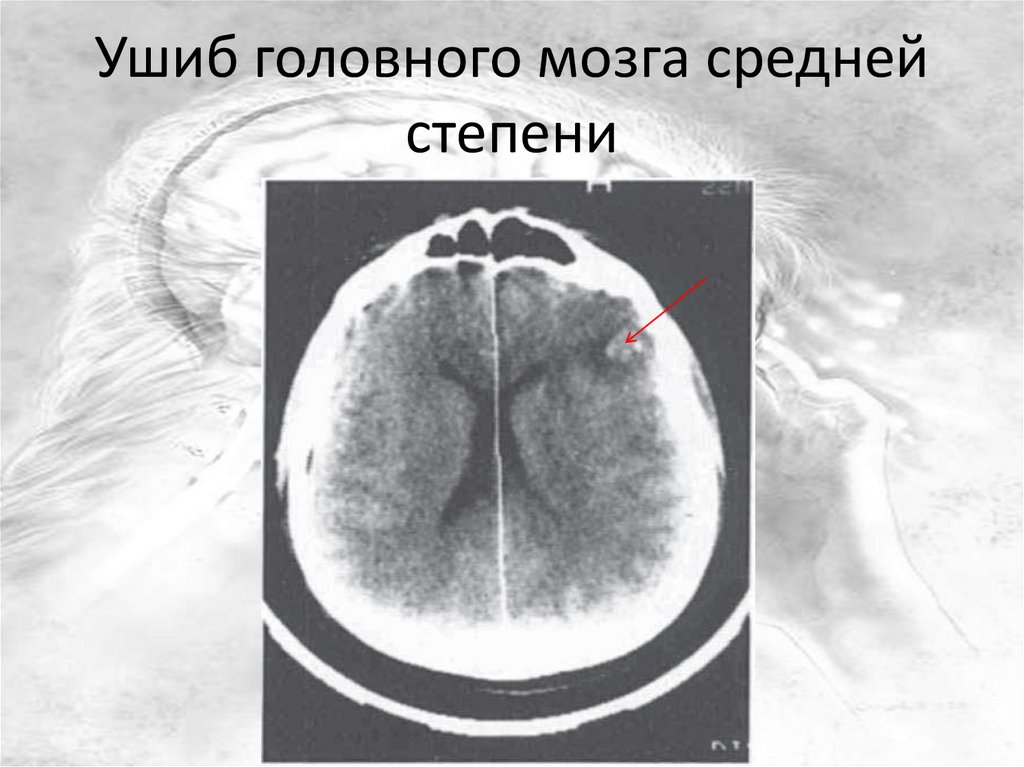

Ушиб головного мозга средней

степени